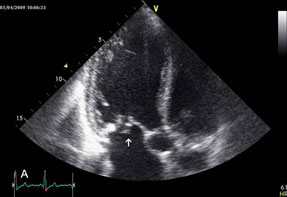

CLINICAL CASE OF ACUTE CHORD RUPTURE OF THE MITRAL VALVE POSTERIOR

rrmedicine.ru

rrmedicine.ru

rupture leaflet mitral posterior figure valve patient chord morbidities clinical acute older case hg pulmonary hypertension mm

Chordal Rupture (2/2) • Video • MEDtube.net

medtube.net

medtube.net

rupture chordal echocardiogram video

Clinical Case Of Acute Chord Rupture Of The Mitral Valve Posterior

www.researchgate.net

www.researchgate.net

mitral leaflet rupture valve posterior chordae clinical acute morbidities patient chord older case